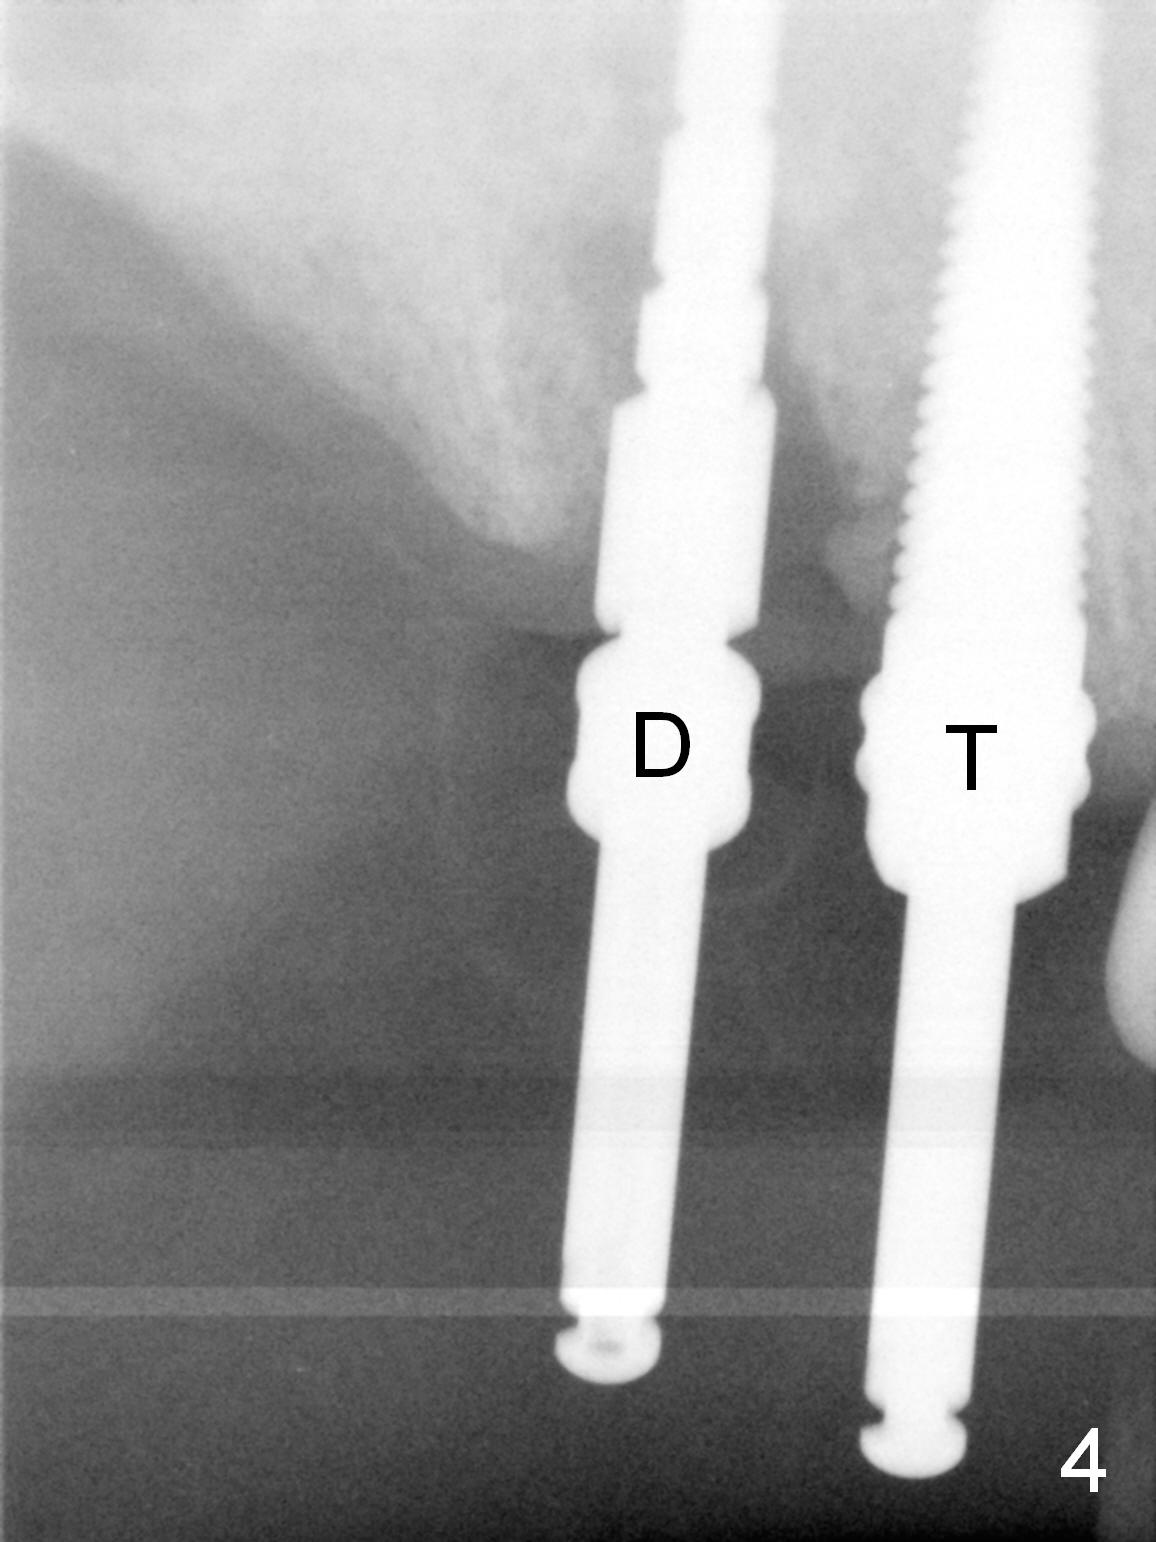

Several of CK's upper teeth (apparently in cross bite) are to be restored with implants (Fig.1). The first two are #5 and 6; note the oval roots (Fig.2). After extraction, and curettage, osteotomy starts in the palatal aspect of each socket. The 1st intraop PA shows that the trajectory at #6 is incorrect (Fig.3). After adjustment, osteotomies look parallel (Fig.4: D: 3.5x20 mm drill; T: 4.5x20 mm tap). This suggests how important it is to use parallel pins to check initial osteotomies for neighboring implants (Fig.3). The trajectory of the implants remains acceptable (Fig.5: 4.5x20 mm with insertion torque »60 Ncm); so is the position of the implants (as palatal as possible; Fig.6 (*: bone graft)). Immediate provisionals are fabricated in cross bite.